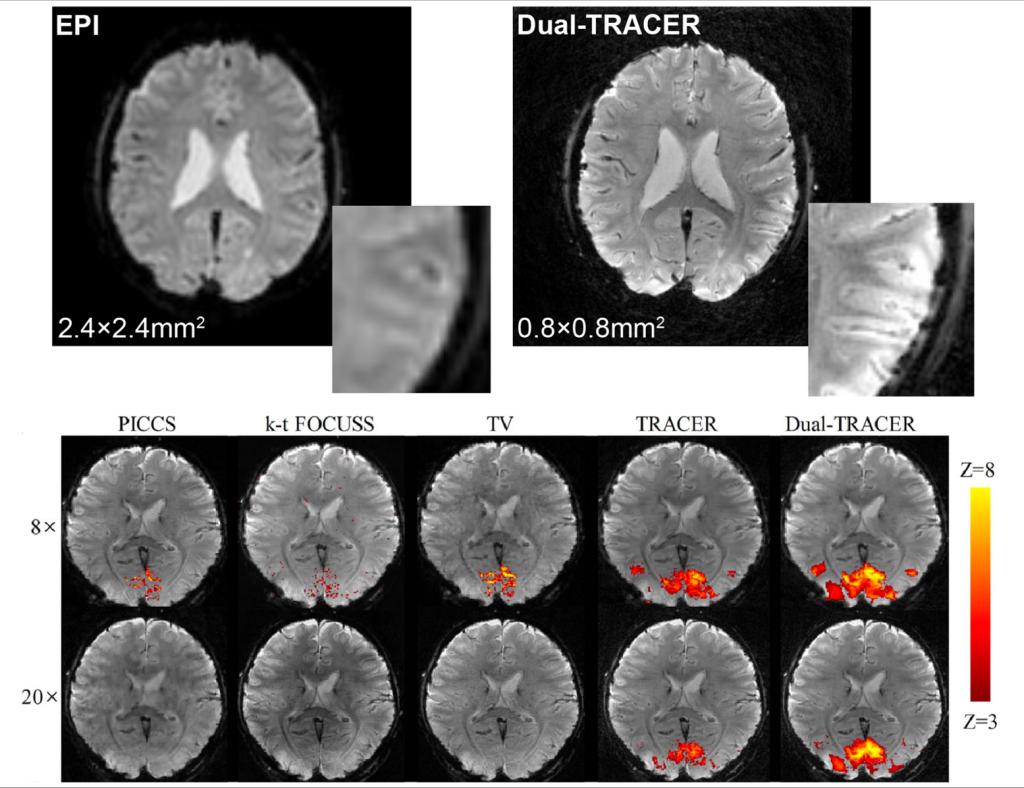

影像中心自成立以来,承担了科技部、国家自然科学基金委、卫生部、北京市科委等近百项国家和省部级项目,收到各种研究经费支持达5000万余元,已发表论文600余篇,发明专利60余项,国际专利10余项,培养学生130余人,获得各种奖励30余项。影像中心已成为全球重要的医学影像尤其是磁共振技术研发中心,开发出大视野高分辨血管壁多对比度成像、三维心肌定量成像、定量血流成像、定量生理成像、无变形高分辨率弥散成像等诸多原创技术,同时这些技术被广泛地应用在多项大规模临床人群队列研究当中形成了针对心脑血管、神经变性性疾病等原创性影像学解决方案。